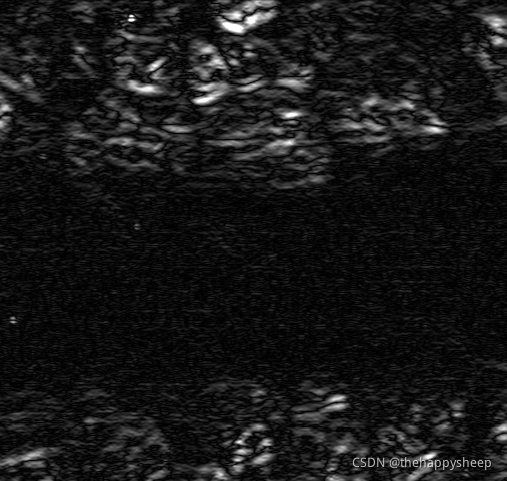

texture_laws (Image, Texture, 'el', 2, 5)

dev_display (Texture)

mean_image (Texture, Energy, 211, 61)

dev_display (Energy)